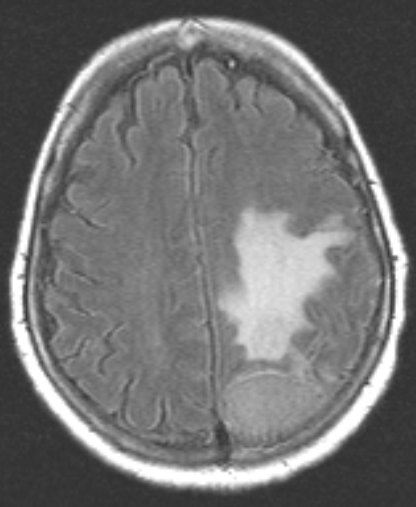

Опухоли после мрт

Опухоли после мрт 113 фото